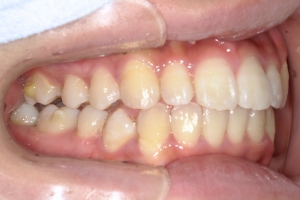

BEFORE

治療前

PROCESS

半年

AFTER

治療後

下の前歯が上あごの歯ぐきに当たるほど噛み合わせが深く、そのことが原因で上顎歯列の正中にすき間(正中離開)が生じていました。部分矯正ですき間を無理やり閉じても、噛み合わせが深いままでは治療後の再発リスクが高くなります。そのため全体矯正で奥歯の噛み合わせを整え、噛み合わせを浅くしつつ前歯を並べました。正中離開は戻りやすい傾向があるので、再発を防ぐため固定式リテーナーを推奨しています。